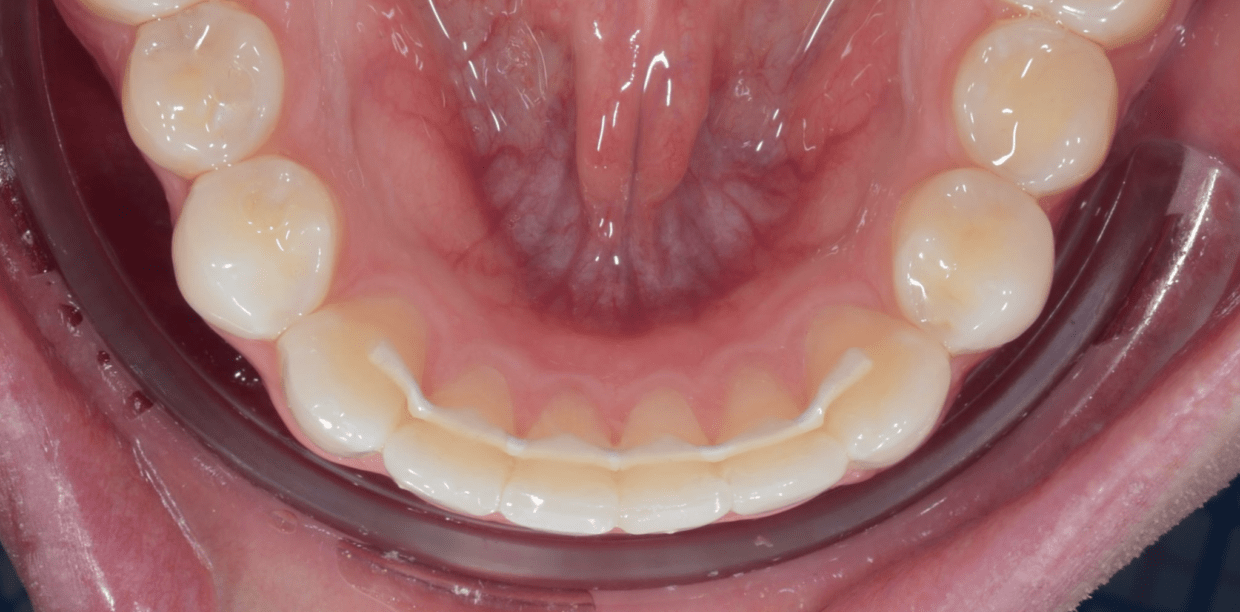

Cas cliniques

Simple - White

Simple - White